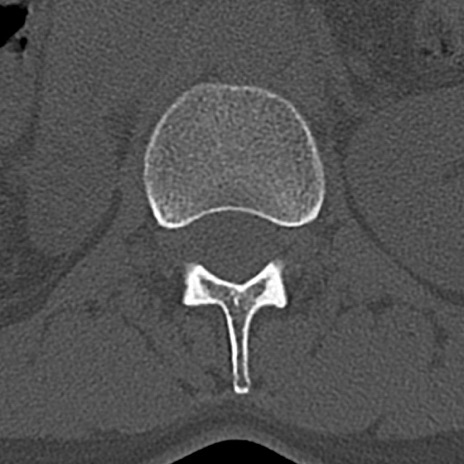

腰椎CT

横断像と矢状断像